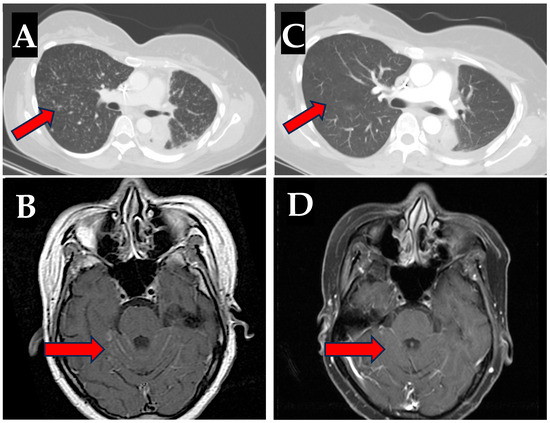

Following her last cycle of maintenance therapy on 16 December 2022, the patient developed severe left-sided chest wall pain. Imaging of the chest, abdomen, and pelvis demonstrated significant disease progression. Osimertinib 80 mg by mouth (PO) daily was subsequently started on 10 January 2023. The patient tolerated this well initially but she was admitted to the hospital on 22 February 2023 with fever, worsening fatigue, and right midback pain. Laboratory studies revealed markedly elevated AST (1113 U/L), ALT (411 U/L), alkaline phosphatase (1088 U/L), and bilirubinemia (3.7 mg/dL). The patient was a never drinker, with negative hepatitis A, B, and C serologies, baseline ALT and AST < 20 U/L on previous labs, and with no known history of previous liver injury. A liver biopsy was taken which demonstrated diffuse lymphocyte infiltration consistent with immune-mediated hepatitis. The patient responded well to high-dose steroids with normalization of liver function following discontinuation of osimertinib and a four-week steroid taper. Targeted therapy was then switched to afatinib in April of 2023, and although she did not experience further hepatotoxicity, her disease rapidly progressed with lymphangitic spread throughout the lungs and significant leptomeningeal disease burden (LMD) (Figure 1A,B), as well as metastases to the liver and bone.

In July 2023, the patient transferred her care to our facility. Liquid biopsy via Guardant360 demonstrated the same Ex19del and T790M mutations as before. With no additional resistance mechanisms detected, we opted to rechallenge with osimertinib in order to simultaneously target both the sensitizing and resistance mutations. Osimertinib was re-introduced at 80 mg PO daily in conjunction with prednisone 40 mg PO daily on 24 July 2023. The prednisone was gradually tapered over 6 weeks and then stopped. This regimen was well tolerated with no laboratory evidence of hepatotoxicity or hepatitis and with minimal reported side effects. Follow-up imaging showed a remarkable response to the osimertinib rechallenge, including a significant improvement in both lung and leptomeningeal disease burden (Figure 1C,D).

Figure 1. Rapid improvement to lymphangitic and leptomeningeal disease with osimertinib. Lymphangitic disease in the lung (A) and leptomeningeal disease burden (B) while on afatinib therapy (June 2023 and July 2023, respectively); leptomeningeal carcinomatosis was noted within the cerebral and cerebellar hemispheres on MRI and innumerable bilateral pulmonary nodules were appreciated on CT. Improvement to both lymphangitic lung metastases on CT (C) and to leptomeningeal disease (D) on MRI after osimertinib rechallenge (August 2023 and September 2023, respectively).